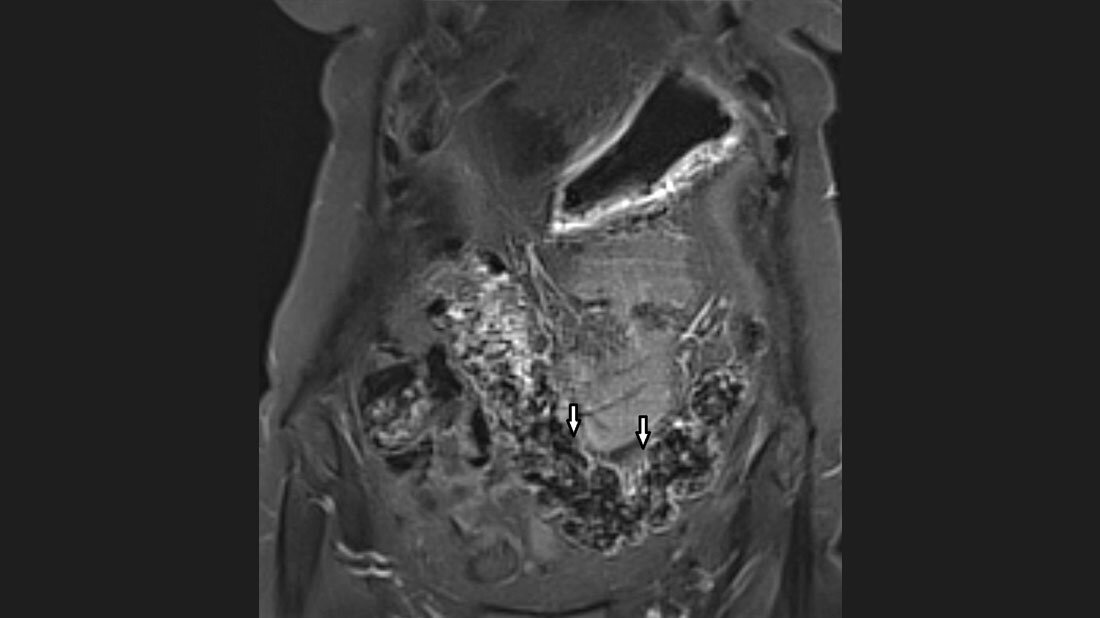

Das Dolichokolon ist eine angeborene Variante des Dickdarms, charakterisiert durch eine Verlängerung und Dilatation, insbesondere des Sigmoids. Es kann eine Symptomtrias mit chronischen abdominellen Schmerzen, Obstipation und Blähungen präsentieren.

Dolichocolon is an inborn anatomic variant, characterized by elongation and also by dilatation of the colon, especially the sigmoid. It can present with a triad of chronic abdominal pain, constipation and bloating.